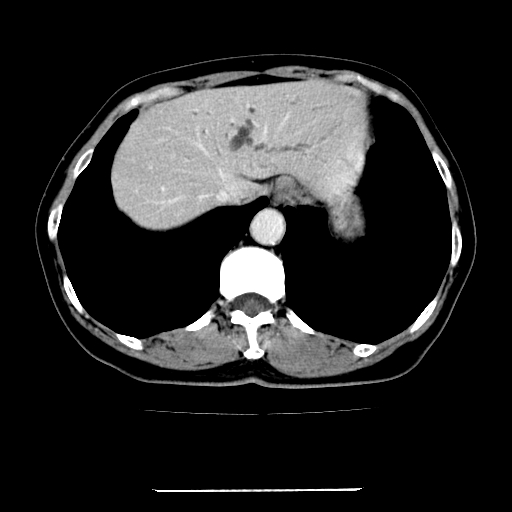

标题: CT22301:女,67岁,上腹部疼痛一周伴皮肤黄染,无发热。 [打印本页]

女,67岁,上腹部疼痛一周伴皮肤黄染,无发热。

考虑肝胆管癌;胰头占位?【形态失常,体积增大】

1、肝门高密度影下层面和胰头层面可见轻度胆管扩张,而静脉和延迟期均未见扫描完胰头,不能完全排除胰头占位。2、肝门部高密度影,考虑钙化或结石。

考虑肝门胆管癌伴门脉左支受侵包埋,建议mrcp进一步检查。